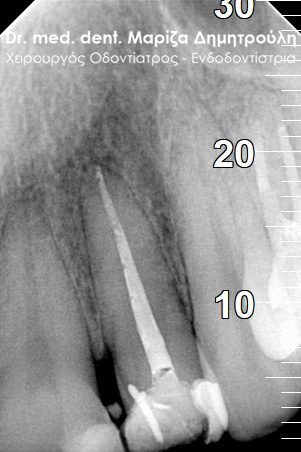

Root canal treatment

BEFORE

AFTER